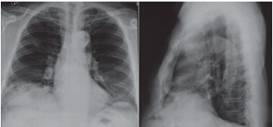

Su radiografía de tórax mostró la interposición de un asa intestinal entre la cúpula diafragmática derecha y la radio densidad hepática correspondiente al signo de Chilaiditi (Ver Figura 2), también se observó lobulación diafragmática derecha y algunos cambios intersticiales peri bronquiales.

Fuente: Archivos radiográficos Cuidados Respiratorios Integrales.

Figura 2 Radiografía del paciente con signo de Chilaiditi.

Se presenta el caso de un hombre adulto mayor, con sintomatología respiratoria crónica como manifestación de la EPOC, quien presentó hallazgos radiográficos compatibles con el signo de Chilaiditi, dado que se observaron las tres características principales: elevación del hemidiafragma derecho sobre el higado, desplazamiento caudal del mismo, e interposición de un asa intestinal. En este caso, el paciente sólo presentó el signo y no cursó con sintomatología gastrointestinal asociada que lo filiara al sindrome, por lo tanto sus síntomas respiratorios fueron explicados por la presencia de la patologia bronquial.